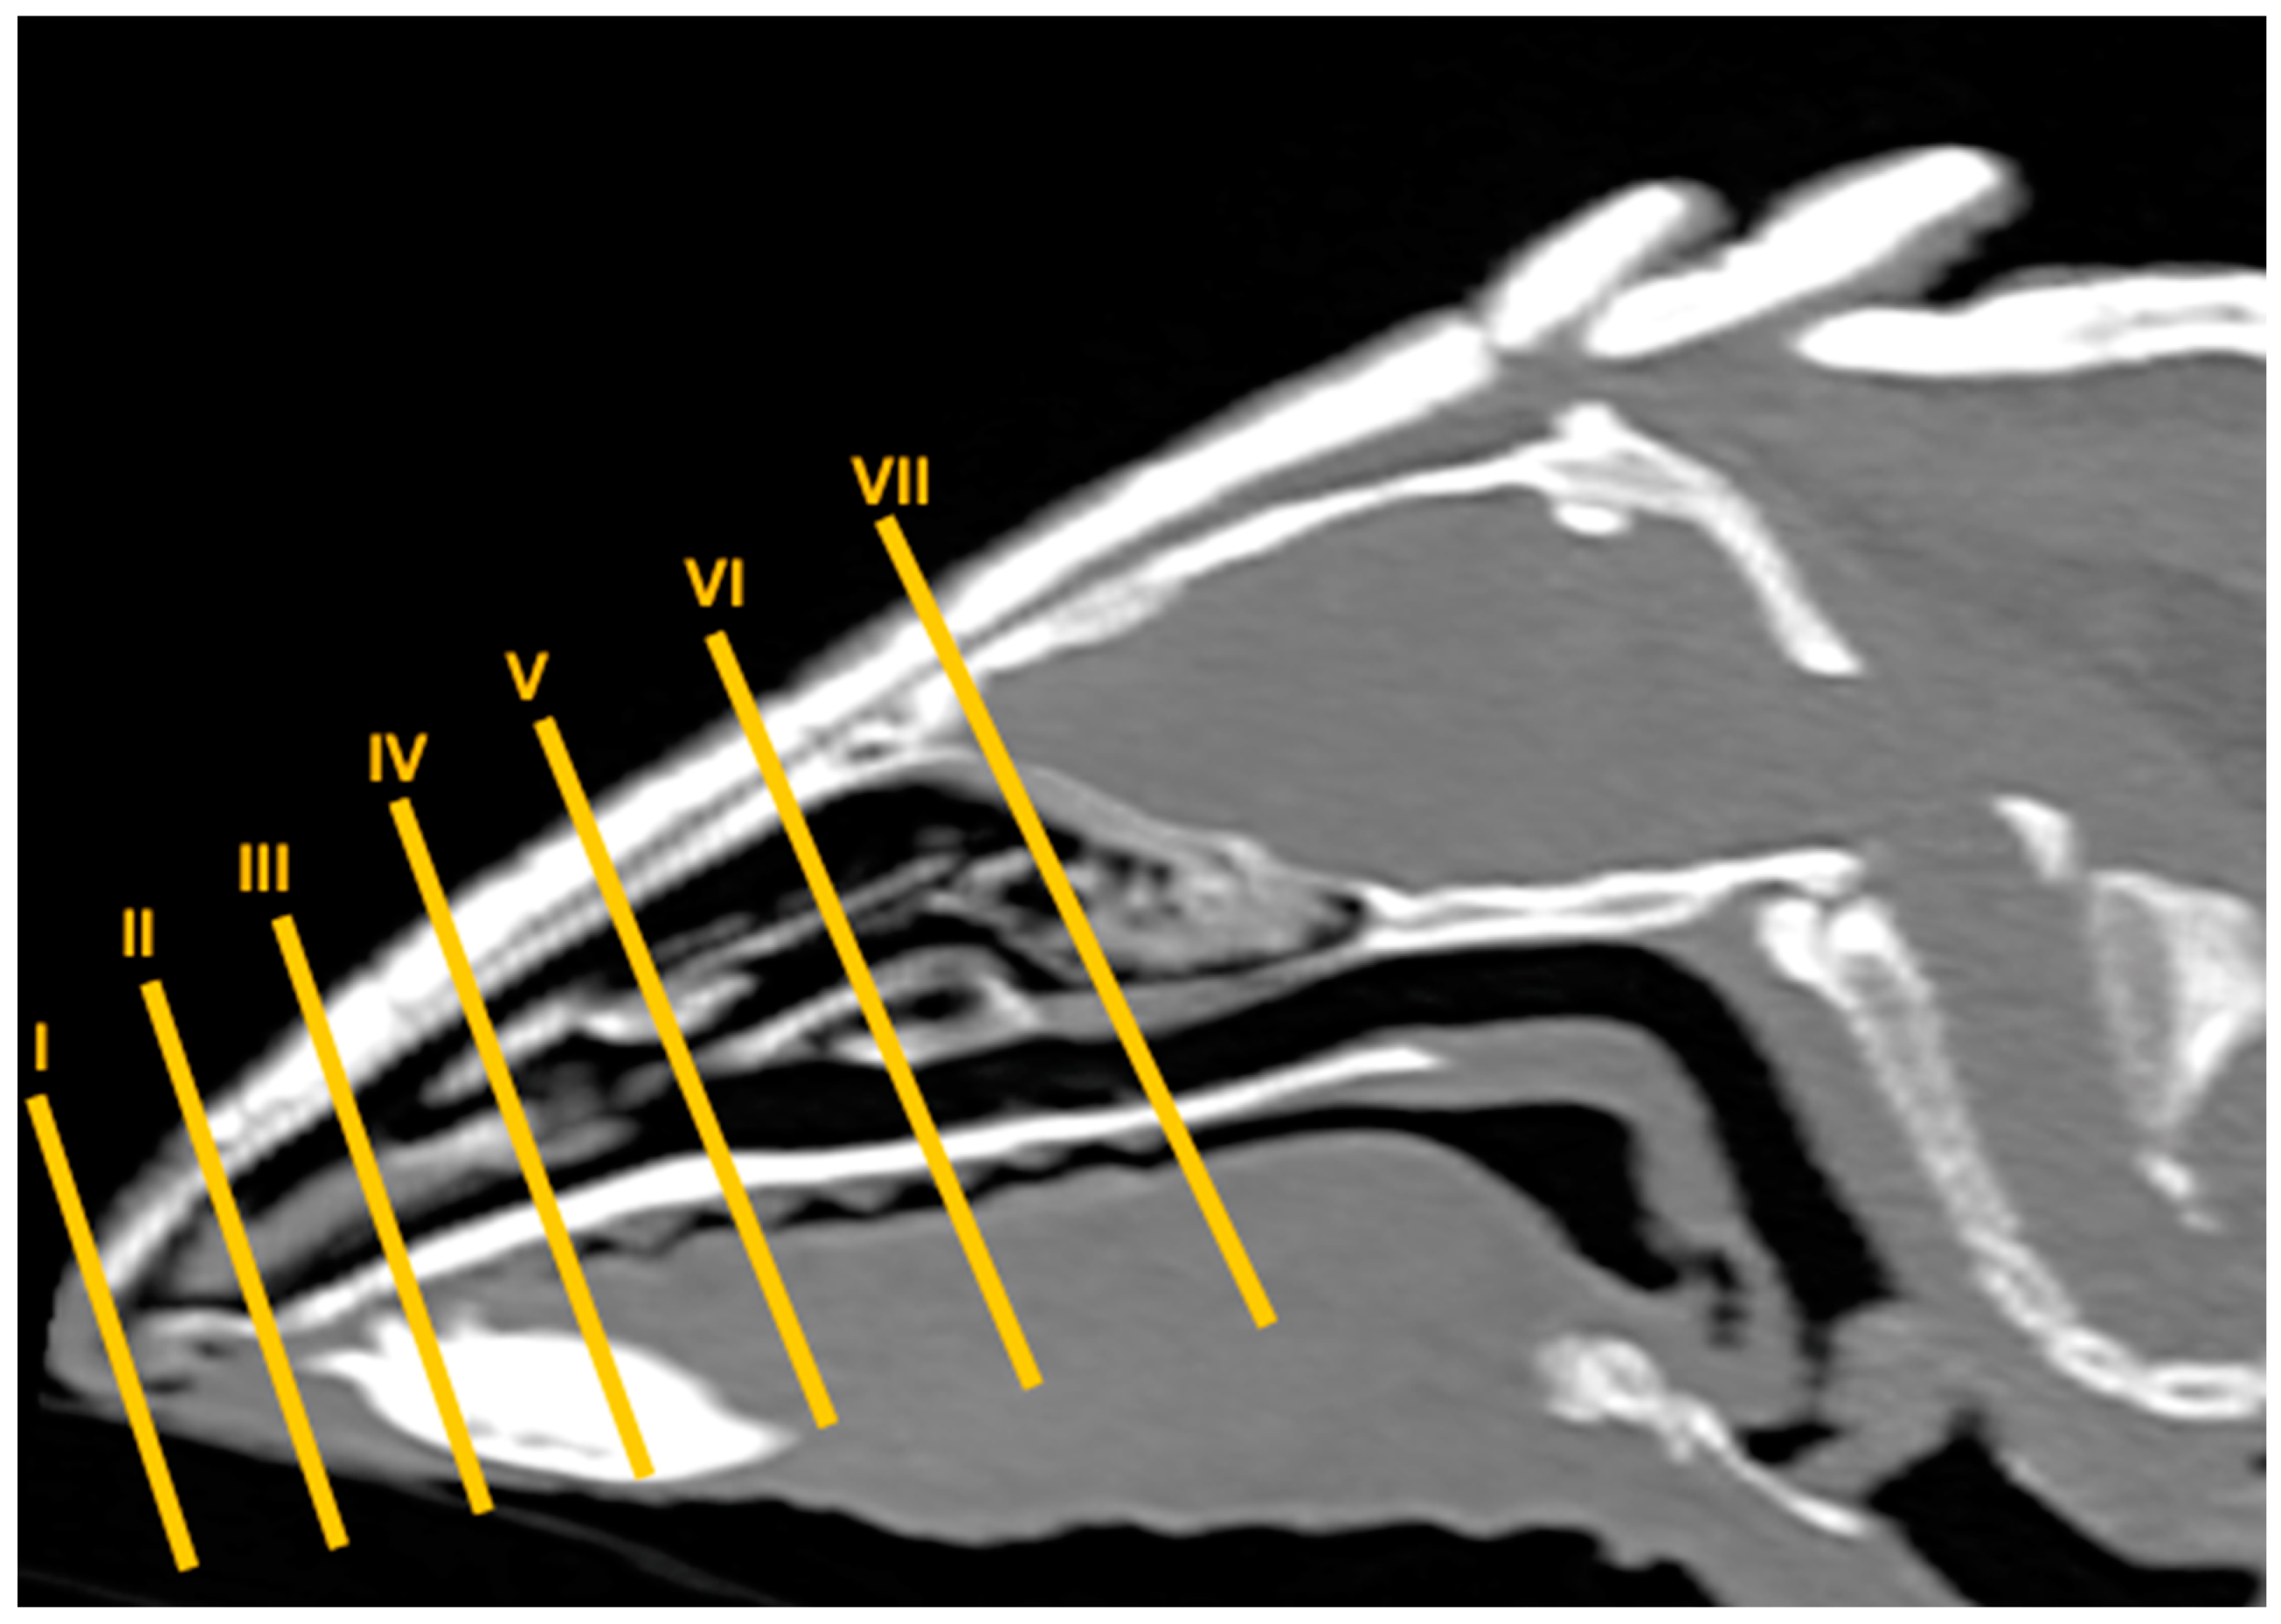

3.1. Anatomical Sections

3.2. Computed Tomography (CT)